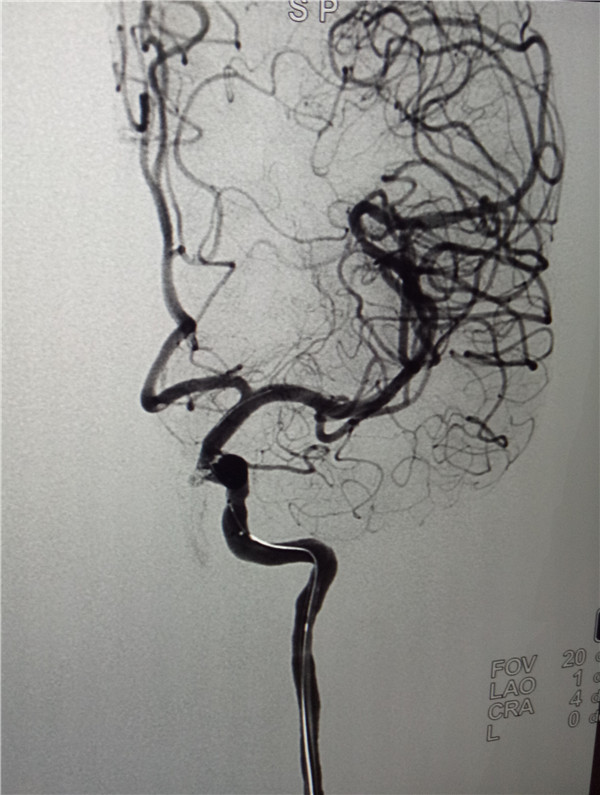

9月5日下午,我院神經(jīng)外科在安醫(yī)附院王曉健主任的幫助下,開展了我院首例顱內(nèi)動脈瘤介入栓塞術(shù),手術(shù)完成順利,術(shù)后造影載瘤動脈通暢,瘤體不顯影。

顱內(nèi)動脈瘤是腦動脈內(nèi)腔局限性異常擴大造成動脈壁的一種瘤狀突出,是造成蛛網(wǎng)膜下腔出血的首要病因,致死致殘率極高,被喻為顱內(nèi)“不定時炸彈”。其首選治療方法為手術(shù)治療,分為開顱動脈瘤夾閉術(shù)和顱內(nèi)動脈瘤介入栓塞術(shù),而動脈瘤介入栓塞術(shù)又有著損傷小,術(shù)后恢復快,效果滿意等優(yōu)點。